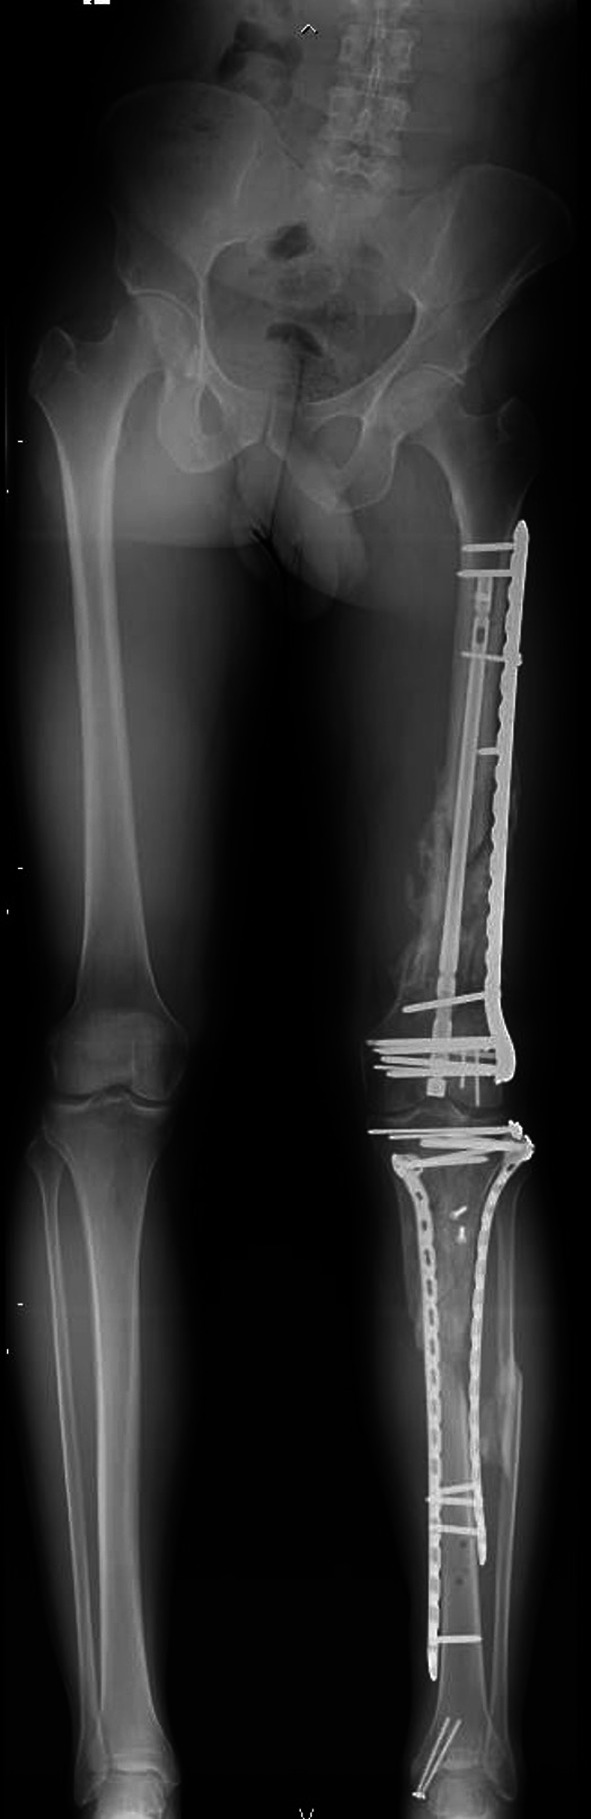

背景:股骨远端骨折是骨科医生面临的一个重大挑战,约占所有股骨骨折的5%。文献中最常报道的联合技术是双钢板技术和逆行钉入加侧钢板,即钉-钢板结构(NPC)。本研究的目的是比较双钢板或逆行内钉加侧钢板治疗33-C骨折的手术数据、生活质量和功能结果。材料和方法:根据加强流行病学观察性研究报告(STROBE)指南进行多中心回顾性观察性研究。诊断是基于AO分类,利用传统的放射学评估。根据患者接受的手术治疗将患者分为两组:NPC组包括接受钉子-钢板结构手术的患者,而Plate组包括接受双钢板手术的患者。结果:共纳入42例患者。鼻咽癌组26例,平均年龄58.4±18.8岁;钢板组16例,平均年龄61.3±16.4岁。在膝关节伸展恢复(p = 0.010)和股骨远端外侧角度(LDFA)方面观察到显著差异(p)。结论:在AO型C型股骨远端骨折中,与双钢板相比,钉钢板结构在膝关节功能和生活质量方面似乎具有明显更好的结果。解剖结果也显示出显著差异,特别是伸展间隙和LDFA。证据水平:III。

Background: Distal femur fractures present a significant challenge for orthopedic surgeons, accounting for approximately 5% of all femoral fractures. Among the most commonly reported combined techniques in the literature are the double-plate technique and the retrograde nailing plus lateral plating, the nail-plate construct (NPC). The aim of our study is to compare surgical data, quality of life, and functional outcomes in 33-C fractures treated with either double-plate constructs or a retrograde nailing plus lateral plate.

Materials and methods: A multicenter retrospective observational study was conducted in accordance with Strengthening the Reporting of Observational Studies in Epidemiology (STROBE) guidelines. Diagnoses were made on the basis of the AO classification, utilizing traditional radiological assessments. Patients were categorized into two groups on the basis of the surgical treatment they received: The NPC group comprised patients who underwent surgery with nail-plate construct, while the Plate group consisted of those who had surgery with double plating.